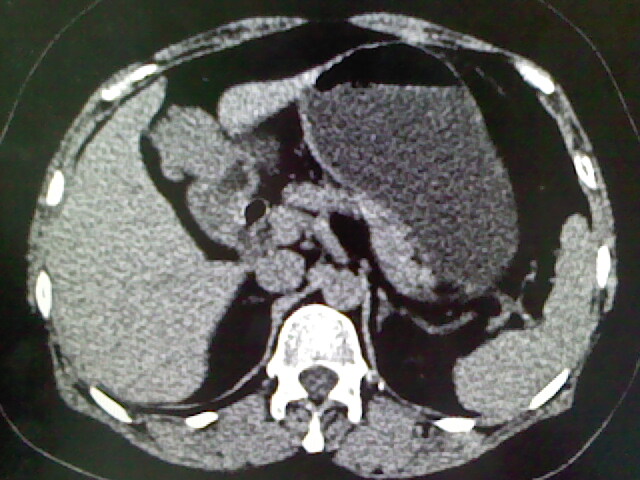

以下是引用卜一在2009-4-2 13:26:00的发言:[br]胆囊颈部结石伴胆囊炎!另:建议增强,待除外肝内占位及胆囊占位!

以下是引用liaoqiang在2009-4-2 16:23:00的发言:[br]胆囊是否切除?胆囊颈区致密影考虑金属夹?结石?肝脏右叶低密度影,考虑增强。